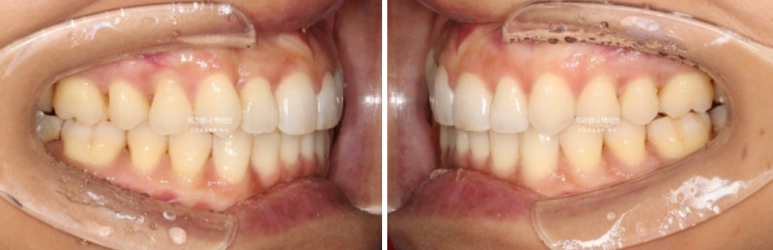

23년 9월 교정치료를 이해 내원하신 분입니다.

고치고 싶은 것은 3가지 입니다.

덧니, 비대칭, 입이 잘 안다물어지는 것

위 아래 앞니 중심선 불일치가 보입니다.

엑스레이를 찍어보면 뼈의 비대칭은 없으나 덧니때문에 위 앞니 중심선이 한쪽으로 쏠려서 비대칭감을 느끼는 상태입니다.

입천장으로 들어가있는 측절치는 아랫니와 반대로 물리는 반대교합 입니다.

덧니가 심하고 입이 잘 안다물어 지기는 하지만 입매 분석시 입술 돌출이 없어서 작은어금니 발치는 하지 않았습니다.

대신 사랑니 공간이 충분해서 사랑니 공간으로 어금니 후방이동을 통해 덧니를 배열하기로 합니다.